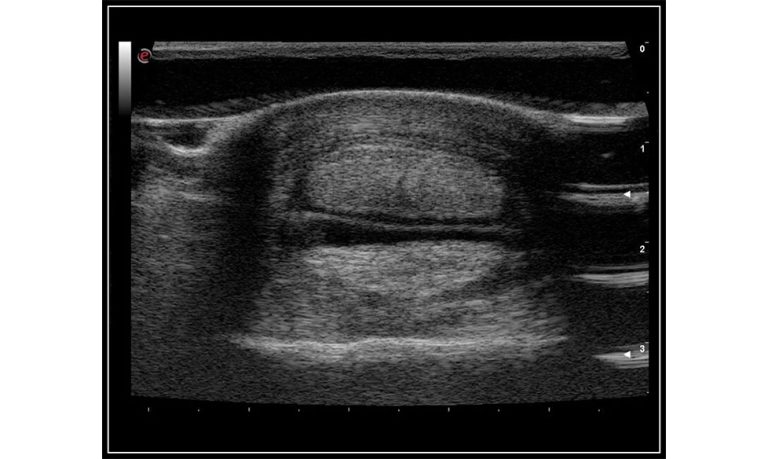

EBIT50/60 VET

All the power you need

The EBit provides all the power you need for today´s challenging clinical environment, yet remain ultra-portable, ultra-affordable. With its cutting-edge imaging technologies, precise and intuitive workflow, ergonomic and eco-friendly design, versatile transducers for all applications from top to toe, we firmly believe the EBit to be the very best portable ultrasound in its class today.